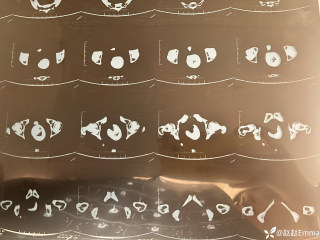

灼见|如果是你,如何处置山东男孩(多器官切除病例)

文/西地兰 特别声明:所有观点仅代表个人言论 特别声明:与当事双方均无利益相关 山东男孩,目前全网沸沸扬扬,看过一些观点,直言不讳地说,大多偏颇。要么一股脑地指责医方的全责,甚至有说千万别在县医院看病。要么又为医方无休止的遮羞,认为这样的手术在县医院做下来已经非常了不起。而我想到的是,以后面临类似的病例,我们怎么办?那么我们不如来一次专业的病案讨论。既然是事后讨论,难免有事后诸葛亮的感觉,但是假如下一次,同行们遭遇这样的病例,如何处置?这是医疗行业所面临的问题。希望我整理的这些思路和相关病例,对同行们有所帮助!就目前的资讯外界不足以判断是否需要急诊,如果需要急诊,那么只能根据术中所见进行处理,

目前知道的消息,第一,术前发现一个血肿,然后做增强CT发现一个占位,没说血肿与肿瘤的关系,术后病理没有描述肿瘤出现破裂出血,大概率就一个小血肿,我就不明白当地主任凭哪个指针去给这小孩开急诊刀的?哪个指南告诉他需要急诊开?第二,诊断不明确他想的不是进一步检查,一边观察一边进一步查,他反而选择腹腔镜探查,这个探查的指针在哪?第三,腹腔一个血肿,没有活动性出血,没有血压心率出现问题,为什么要开腹进去碰它?不能等血肿吸收再明确肿瘤性质吗?第四,1点进腹,3点病理结果出来,按这个时间还算顺利,应该还没出事,孩子还算平稳,病理是低度恶性,切了就治愈,他一年能开几台这手术,就敢继续做,拿孩子练手。第五,后面

2023年10月26日,来自山东菏泽市成武县的小烨和他家人的命运被彻底改变了。这个原本阳光、可爱的小男孩在一次意外被撞击后,在医院检查出了腹腔内存在肿瘤,并在手术中被切除了包括十二指肠、胰腺、大部分胃和小肠等多个器官。此后便无法再像正常人一样吃饭、喝水,活着要靠长期静脉注射营养液。一份2024年12月由第三方机构出具的司法鉴定意见书显示,当时给小烨做手术的成武县人民医院在该医疗行为中存在过错,与小烨的损害后果之间存在因果关系,建议医疗过错在损害后果中的原因力大小为同等原因。此外,另一份由成武县卫生健康局在2025年9月28日发出的书面答复中显示,成武县人民医院存在24小时内未完成病历;手术知情